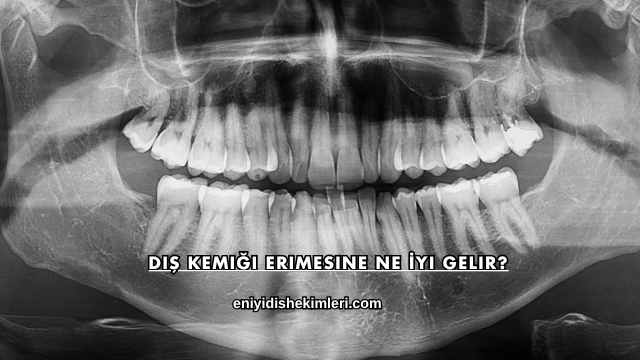

Diş Kemiği Erimesine Ne İyi Gelir?

Diş kemiği erimesi, zaman içinde çene yapısının zayıflamasına ve dişlerin desteğini kaybetmesine neden olan önemli bir ağız sağlığı sorunudur. Düzenli bakım, doğru beslenme ve profesyonel tedaviler bu süreci yavaşlatmada etkili olurken, günlük alışkanlıkları iyileştirmek de kemik dokusunun korunmasına katkı sağlar. Ağız hijyenine dikkat eden kişiler, çene kemiğinin güçlenmesine yardımcı olacak adımlarla daha sağlıklı bir ağız yapısına ulaşabilir.

Diş kemiği erimesine iyi gelen yöntemler genellikle çene yapısını güçlendirmeye, iltihap riskini azaltmaya ve kemik yenilenmesini desteklemeye odaklanır. Düzenli diş hekimi kontrolü, besin açıdan zengin bir beslenme düzeni ve ağız bakımının doğru yapılması, kemik dokusunun daha dirençli hale gelmesine yardımcı olur. Klinik destekler ile günlük bakım birleştiğinde, kemik kaybının ilerlemesi büyük ölçüde yavaşlatılabilir ve ağız sağlığı dengede tutulabilir.